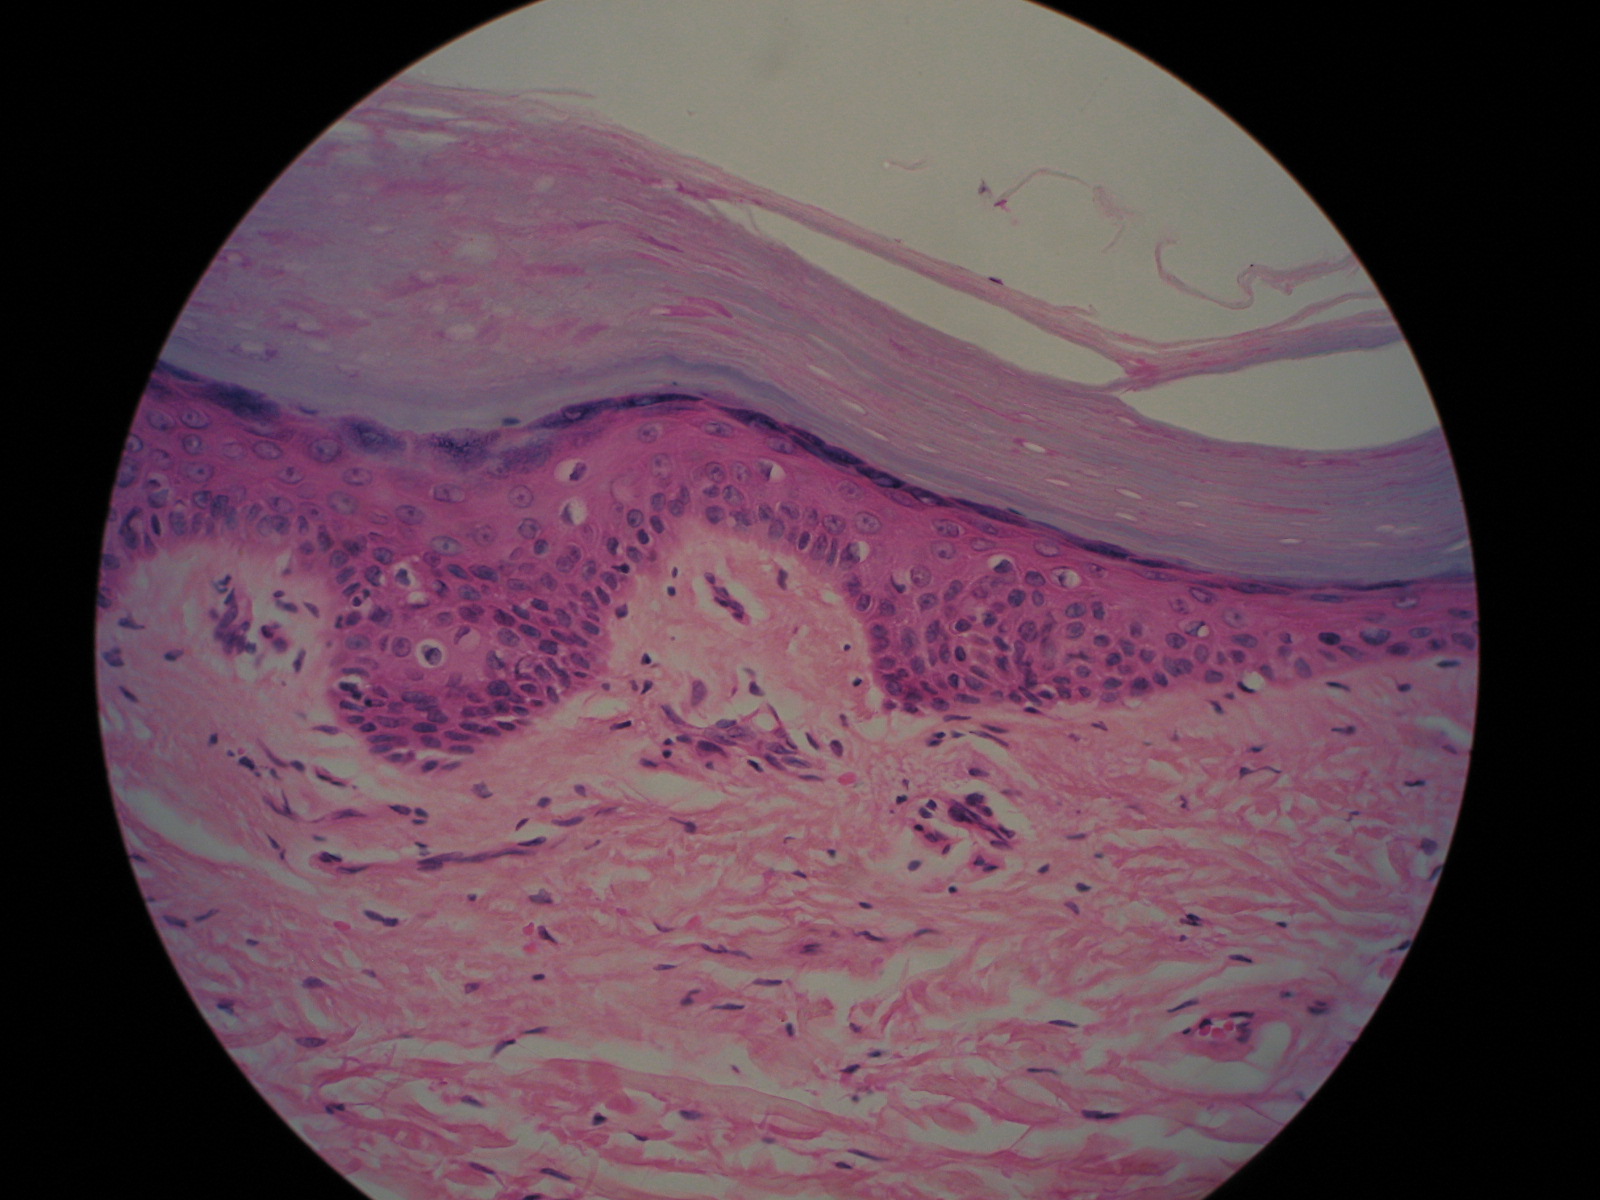

Identify the pigment and layers.,  | melanin; epidermis- stratum corneum, granulosum, spinosum, basale; Dermis- papillary, reticular |

Identify the layers.,  | Epidermis- stratum corneum, lucidum, granulosum, spinosum, basale; Dermis- papillary, reticular |

Name the tissue types for each of the layers.,  | Epidermis- keratinized stratified squamous; Papillary- areolar; Reticular layer- dense irregular |